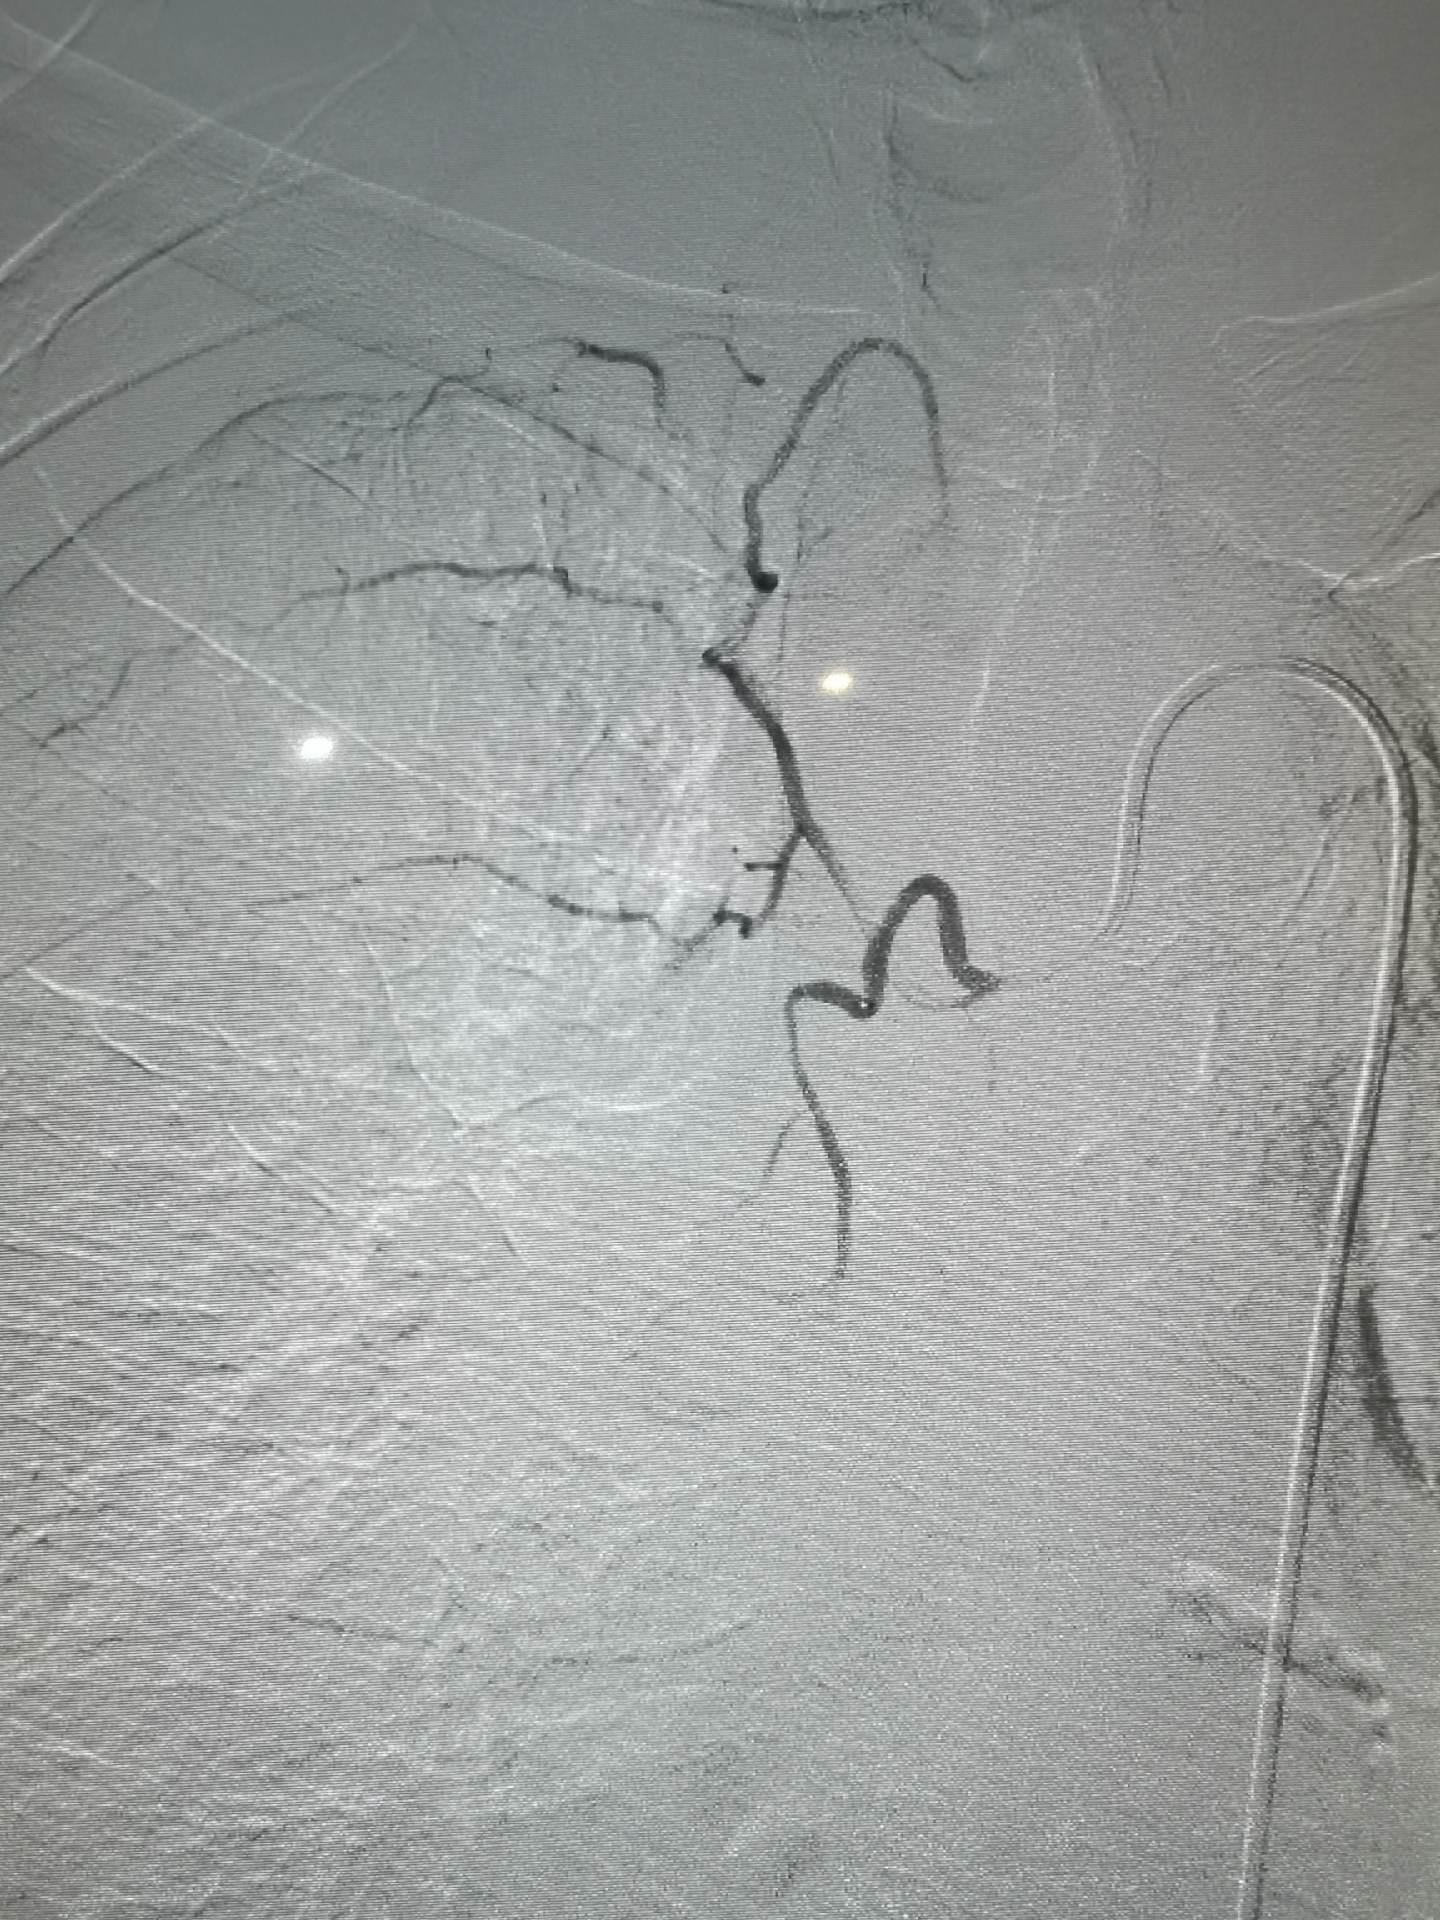

肺癌伴两肺转移,癌性淋巴管转移,体肺动脉化疗,支气管动脉联合肺动脉置管化疗。